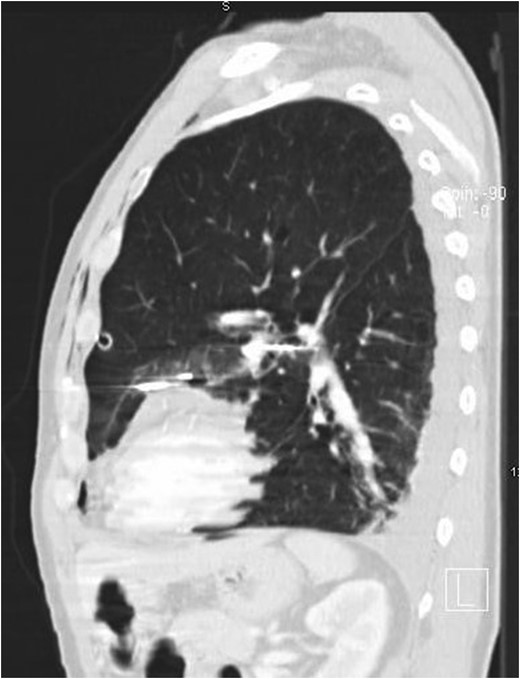

A 64-year-old man referred to our institution with self-inflicted penetrating chest injuries with an electric nail gun. This was in response to express his frustration towards an expensive non-functioning product purchase. Patient used an electric driller to fire in three nails on the chest between left anterior axillary line and left lateral sternal border. Upon arrival to emergency department, on initial assessment according to ATLS protocol, his Glasgow coma score (GCS) was 15, hemodynamically stable with three puncture wounds in his chest medial to his left nipple. He also sustained full thickness electrical burns on the left middle and index fingers and fractured right middle, ring and little fingers. Chest radiograph showed three nails of close proximity to the heart, and a left sided pneumohaemothorax. A chest drain was inserted and a CT thorax was performed (Figs 1 and 2).

The patient underwent a sternotomy for removal of the three nails. Two nails were easily visible and removed. They caused pericardial perforation and myocardial injury. The third nail was difficult to locate. Myocardial injury showed a trajectory near the junction of the left anterior descending artery and the diagonal artery with no bleeding appreciated. A magnet was then used to locate the third nail which was found to be deep in the hilum of the lung. The magnet was then used to gently ‘milk’ the nail into a more superficial position. Once the nail was more easily accessible, it was removed.